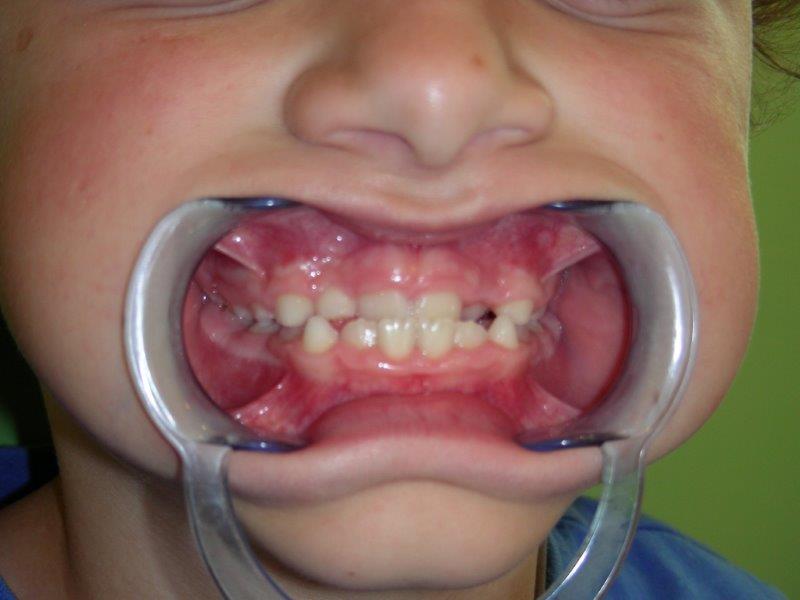

doble dentición DOBLE DENTADURA

falta espacio colmillos APIÑAMIENTO, falta de espacio para el correcto alineamiento de los dientes.

falta de espacio para el incisivo lateral FALTA DE ESPACIO PARA LOS CANINOS